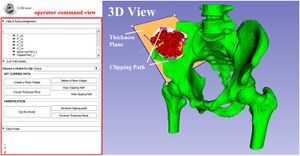

Publication: PLoS One. 2016 Jan 11;11(1):e0145987. PMID: 26751685 | PDF Authors: Zhan Q, Chen X. Institution: School of Mechanical Engineering, Shanghai Jiao Tong University, Shanghai, China. Background/Purpose: This paper proposes an interactive method of model clipping for computer-assisted surgical planning. The model is separated by a data filter that is defined by the implicit function of the clipping path. Being interactive to surgeons, the clipping path that is composed of the plane widgets can be manually repositioned along the desirable presurgical path, which means that surgeons can produce any accurate shape of the clipped model. The implicit function is acquired through a recursive algorithm based on the Boolean combinations (including Boolean union and Boolean intersection) of a series of plane widgets' implicit functions. The algorithm is evaluated as highly efficient because the best time performance of the algorithm is linear, which applies to most of the cases in the computer-assisted surgical planning. Based on the above stated algorithm, a user-friendly module named SmartModelClip is developed on the basis of Slicer platform and VTK. A number of arbitrary clipping paths have been tested. Experimental results of presurgical planning for three types of Le Fort fractures and for tumor removal demonstrate the high reliability and efficiency of our recursive algorithm and robustness of the module. Funding:

A snapshot of the module SmartModelClip in 3D Slicer. On the left is the operator command view that users can create and manipulate clipping path and thickness plane(i.e., they can create, hide and delete plane widgets). Users can also reverse the directions of the axes of the both clipping path and thickness plane widget. On the right is the scene that users can interact with the clipping path. They can specify the fiducial points that position the clipping path and modify the boundary of the clipping path by dragging the handles to obtain the desirable clipping path. |